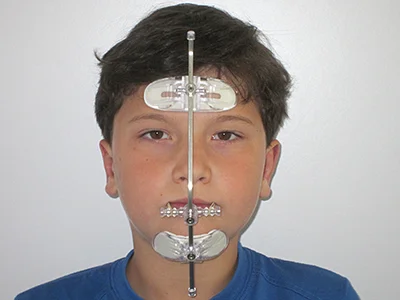

Obličejová maska

Obličejová maska